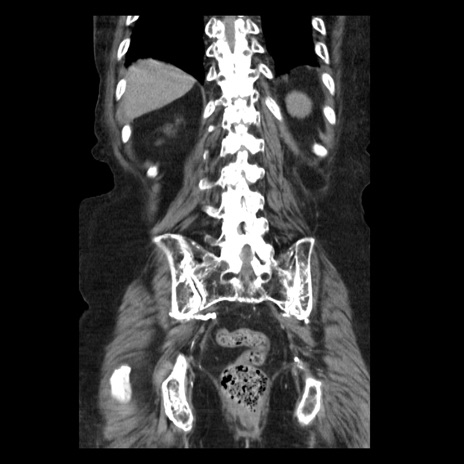

症例14(冠状断像)

【症例】 90歳代女性

【主訴】 腹痛・嘔吐

【現病歴】今朝から左側腹部痛を認めた。 経過観察していたが、嘔吐を認めたため来院。

【既往歴】 子宮癌術後

【身体所見】 意識清明、BP 127/54mmHg、P 98bpm Sp02 95%(RA)、BT 35.8°C、腹部平坦・軟腸ぜん動音聴取良好、右下腹部圧痛(+) 反跳痛なし

【データ】WBC 9800、CRP 0.46